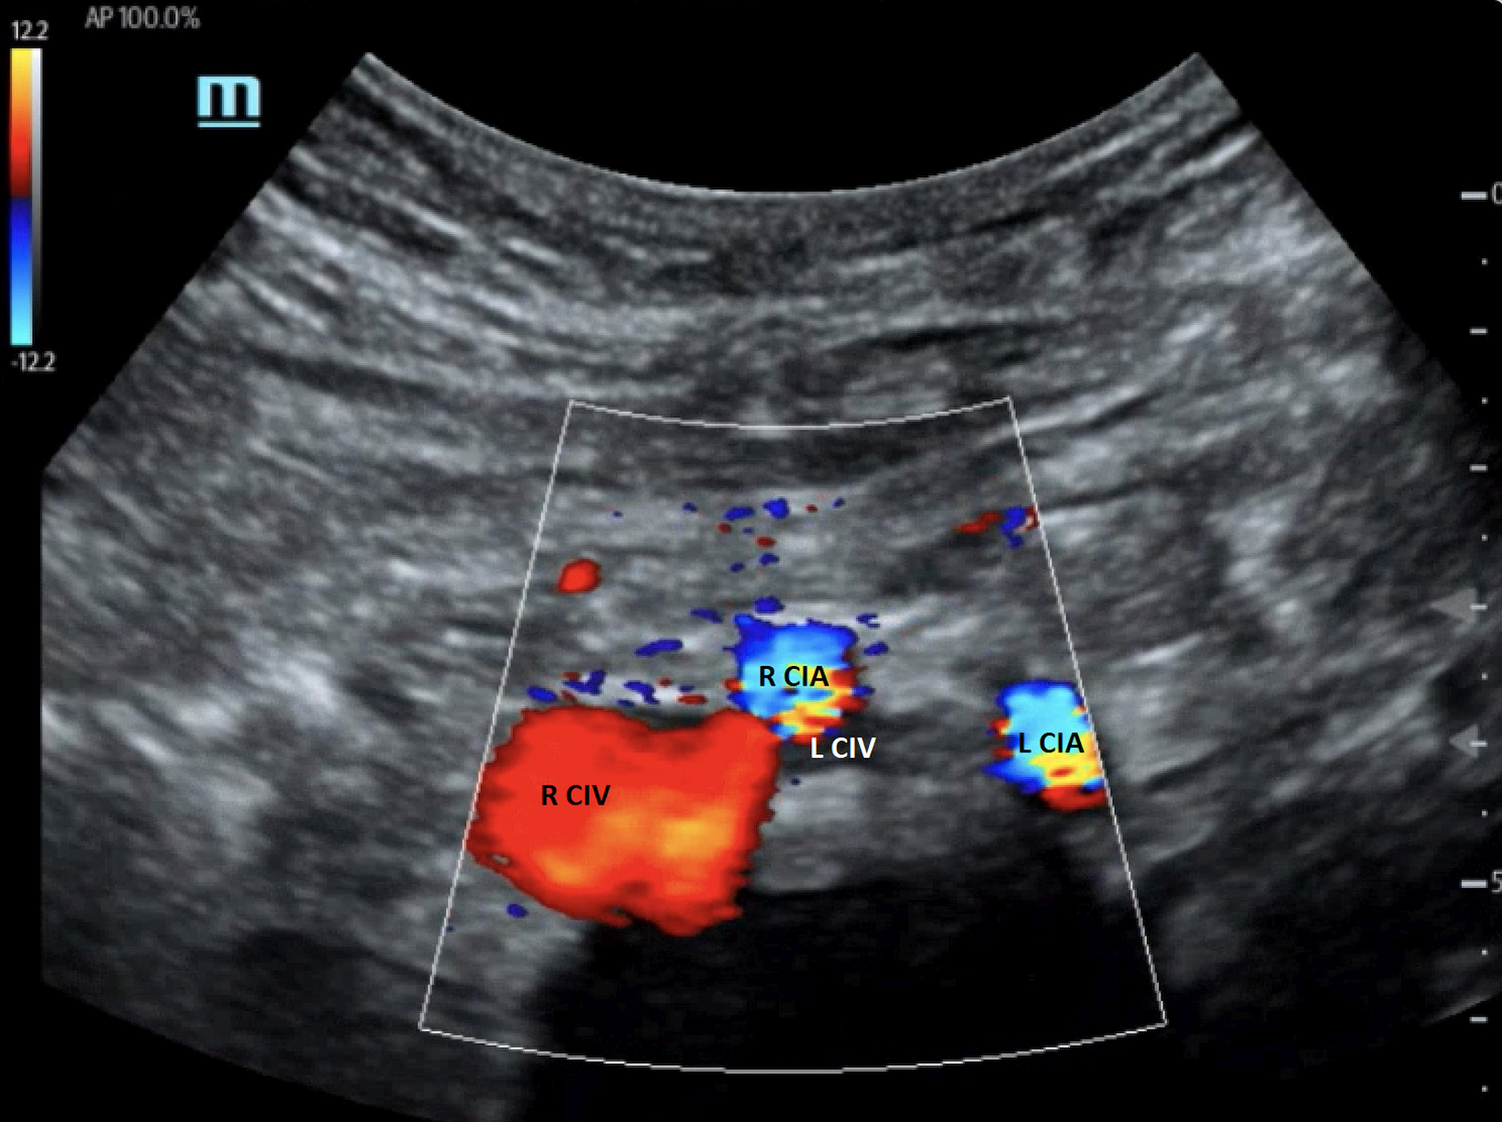

The compression of the left CIV by the right CIA can be demonstrated with duplex ultrasound when a good acoustic window is obtained (38, 39). Figure 7 shows the anatomical relationship of the right and left CIAs and CIVs. In this image, the left CIV is compressed by the right CIA. However, direct visualization of a severe stenosis of the left CIV at the point that the right CIA crosses the vein is not always possible on B-mode ultrasound imaging. Duplex ultrasound may demonstrate venous flow without respiratory variation in the iliac vein below the compression point, and flow velocity increases at the location of the right CIA compressing the left CIV (40). If the PSV gradient is more than 2.5, the findings are significant. Flow reversal in the ipsilateral internal iliac vein can be associated with CIV compression (3, 41). The first clinical presentation of some patients with IVCS can be left iliac vein thrombosis. Confirming the presence of deep vein thrombosis may not be difficult, but demonstrating the left iliac vein compression is not generally possible when the vessel is thrombosed.

Figure 7

Color Doppler image of iliac vein compression syndrome. The left common iliac vein (L CIV) is compressed by the right common iliac artery (R CIA). R CIV, right common iliac vein; L CIA, left common iliac artery [From: Brown et al. (39). Reprint under a Creative Commons Attribution 4.0 International License].